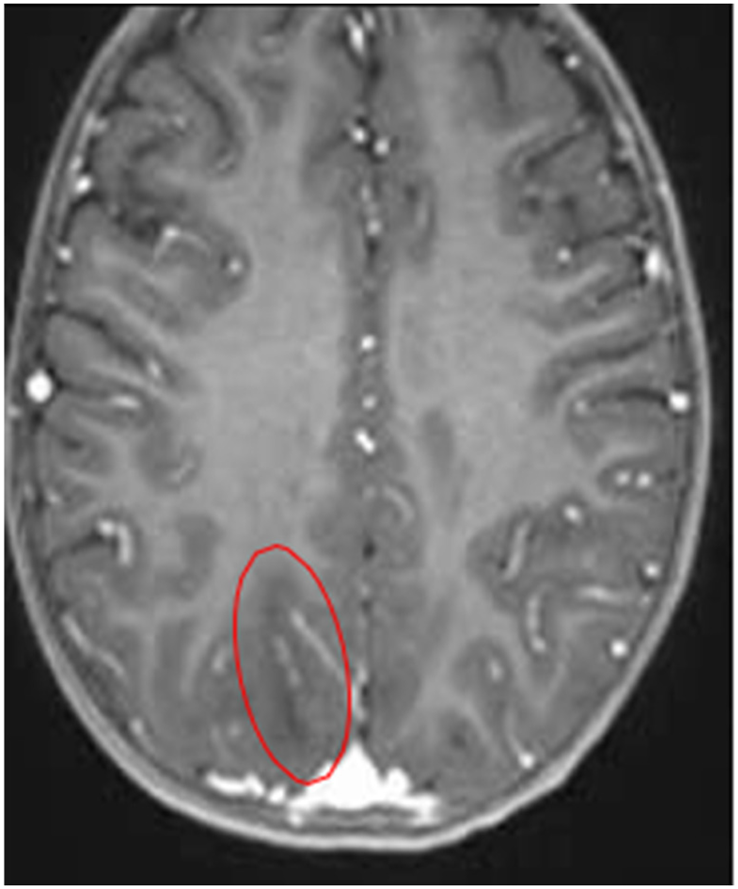

Quadrant C: T1/ADC sequence – contrast-enhanced

|

| A hypointense focus is observed in the right subcortical postcentral parietal region Probable areas of demyelination are suspected - Suggesting a possible diagnosis of encephalitis |

Abnormalities in gray-white matter differentiation are observed Hyperintense images are observed in the subcortical white matter – in the following regions: Bilateral occipital Bilateral parieto-occipital |